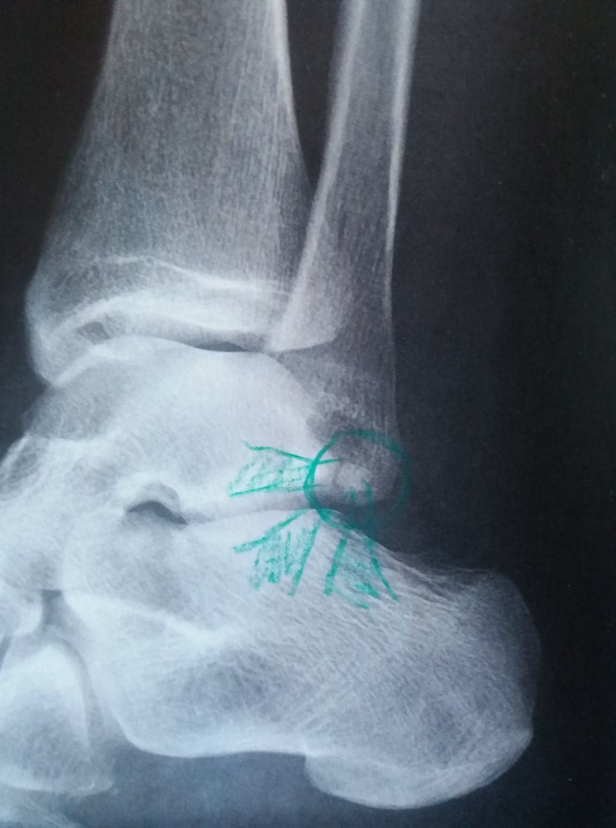

Långfredag i skärgården. Kraftig vrickning. 6-8 veckors läkning säger läkaren efter röntgen. Avslitna ligament och en lös benflisa.